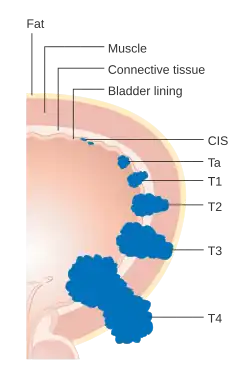

O sistema de graduação de 1973 da OMS para os CCTs (papiloma, G1, G2 ou G3) é mais comumente utilizado: Os CCTs de bexiga são classificados em:

- Ta Tumor papilar não-invasivo

- T1 Invasivo, mas não chega até a camada muscular da bexiga

- T2 Invasivo, chega até camada muscular

- T3 Invasivo, ultrapassa a camada muscular até a camada gordurosa externa da bexiga

- T4 Invasivo, chega a invadir estruturas da região como a próstata, útero ou parede pélvica

- Estágio 0: Células cancerosas são encontradas somente no revestimento interno da bexiga.

- Estágio I: Células cancerosas se proliferaram para a camada abaixo do revestimento interno mas não para os músculos da bexiga.

- Estágio II: Células cancerosas se proliferaram para os músculos na parede da bexiga mas não para o tecido gorduroso que circunda a bexiga urinária.

- Estágio III: Células cancerosas se proliferaram para o tecido gorduroso que circunda a bexiga urinária e para a próstata, vagina ou útero, mas não para os linfonodos ou outros órgãos.

- Estágio IV: Células cancerosas se proliferaram para os linfonodos, parede abdominal ou pélvica e/ou outros órgãos.